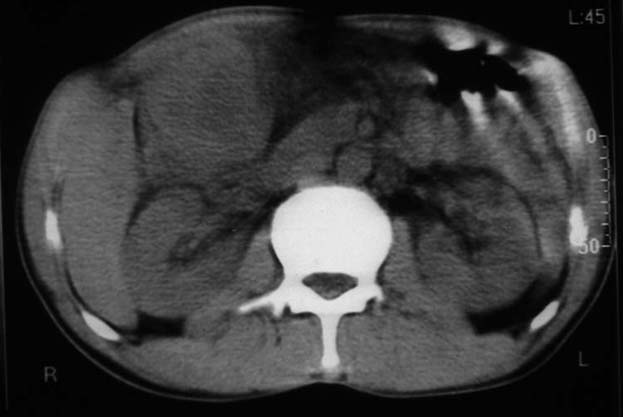

男,50y,右上腹包块痛10天,查:右上腹饱满,右肋下触及6*6cm大小包块,质硬,压痛。患者诉:10天前感冒胸闷,痛,后痛及右上腹部,既往有肝炎病史。

没有增强!只能考虑左叶内侧段巨块型肝癌(外生型)可能性大;胆囊呢?不除外胆囊癌累及肝脏。

我倒是先考虑胆囊癌(肿块型)肝脏受侵可能性大,做个c+

病变位于胆囊窝内,其内密度不均,肝总管及胆总管扩张,胃里面没有清水充盈,不解为什么楼主不做好了准备再做呢,支持:“左叶内侧段巨块型肝癌(外生型)可能性大;不除外胆囊癌累及肝脏”建议增强吧。

考虑:肝左内叶巨块型癌,主动脉旁淋巴结转移.(有一层面似见胆囊受压.)